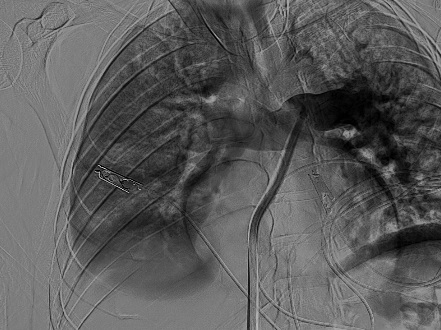

سجل مجمع الدمام الطبي أحد مكونات تجمع الشرقية الصحي ، إنجازاً طبياً نوعياً بعد نجاح فريق الأشعة التداخلية في إنقاذ حياة مريض كان يعاني من جلطة رئوية حادة وكبيرة شكّلت خطراً مباشراً على حياته ، وذلك باستخدام تقنية طبية متقدمة دون الحاجة إلى جراحة قلب مفتوح .

وكان المريض قد نُقل بشكل إسعافي من أحد المستشفيات وهو في حالة حرجة ، نتيجة معاناته من ضيق شديد في التنفس وانخفاض حاد في مستوى الأكسجين ، إثر انسداد كامل في الشريان الرئوي الرئيسي بسبب خثرات وريدية عميقة ظهرت بعد خضوعه لعملية منظار لمفصل الركبة.

وبفضل سرعة الاستجابة وجاهزية فريق الأشعة التداخلية جرى التدخل العلاجي العاجل وفتح الشريان الرئوي وسحب الجلطة بالكامل بدقة عالية ، ما أدى إلى تحسّن فوري في العلامات الحيوية واستقرار الحالة دون تسجيل أي مضاعفات.